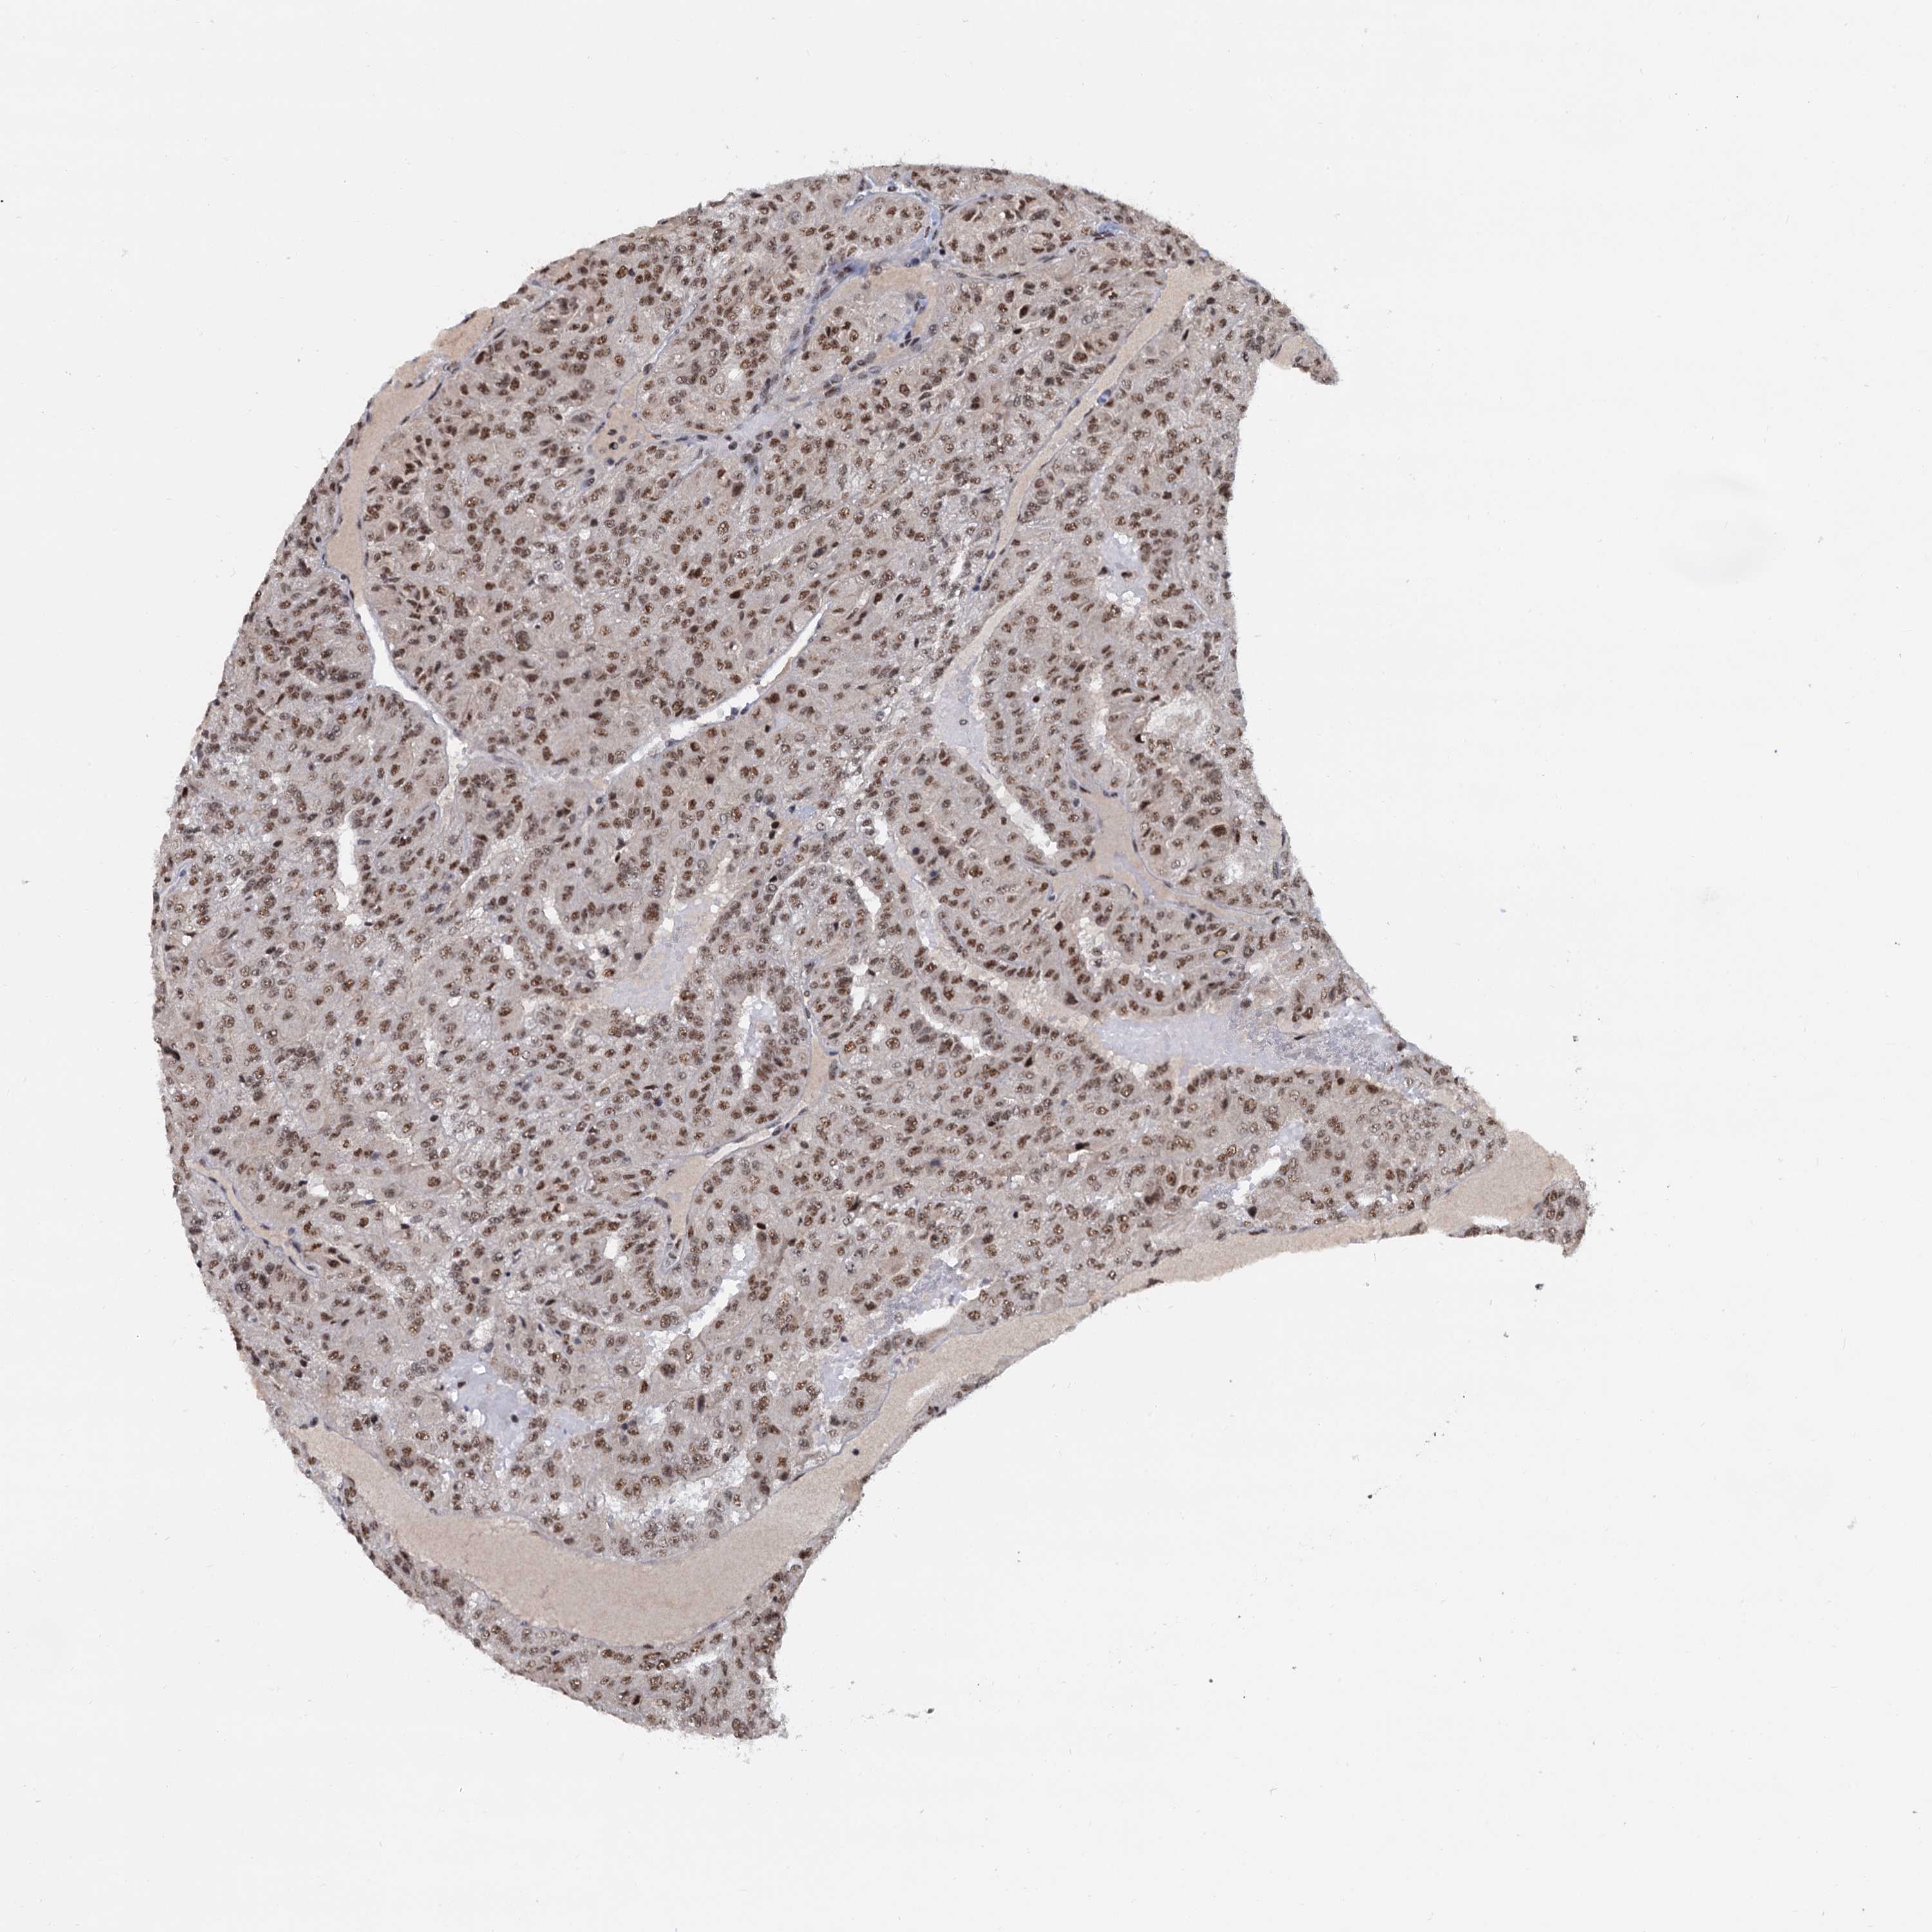

Renal cancer

Kidney chromophobe